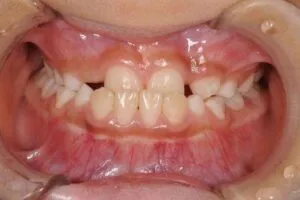

通常、前歯は上の前歯が下の前歯よりも前に生えているのが正常です。

この状態が反対になってしまっている状態を反対咬合といいます。

この状態では見た目もですが前歯をうまく使うことができないので奥歯にかかる

負担が増えてしまいます。

このような前歯のかみ合わせの状態を反対咬合といいます。